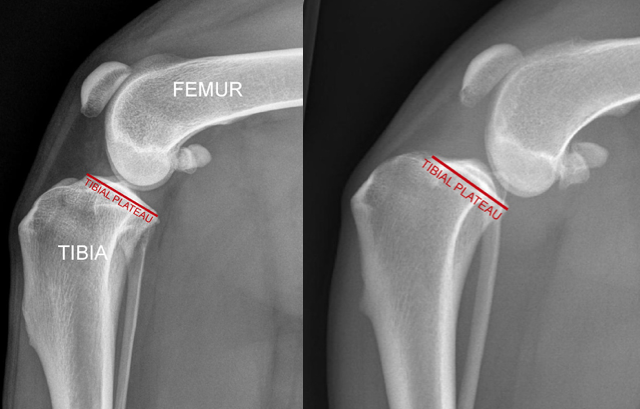

The top of the dog’s tibia (referred to as the tibial plateau) is sloped downhill and backwards, typically at about 30 degrees. Because of this 30-degree slope of the proximal tibia, the femur wants to slide off the back of the tibia. These characteristics are shown in the next figure.

The image to the far left shows a normal dog knee and the tibial plateau, which is typically sloped down-hill and backwards at about 30 degrees. In that dog the cranial cruciate ligament is intact and so the femur remains perched on top of the tibia. However, the mechanical impetus is for the femur to slide off the back of the tibia (think of a ball on a hill) and this is what happens if the cranial cruciate ligament is ruptured, as in the second radiograph.